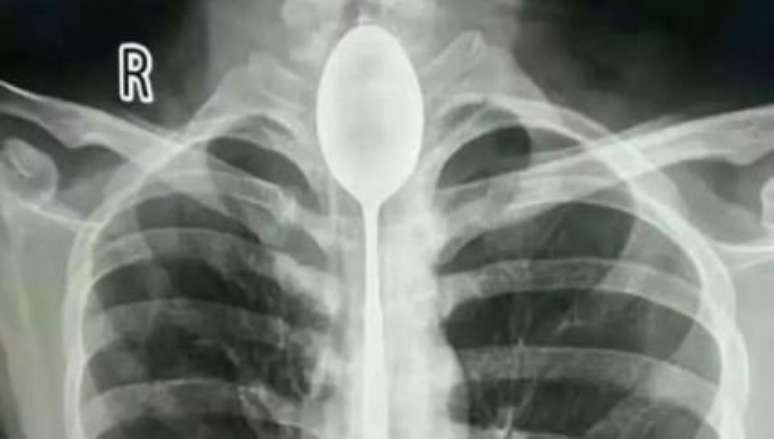

Foto: Divulgação/Xinjiang Meikuang General Hospital

Um chinês, chamado Zhang, engoliu uma colher de aço durante um desafio em 2017. O utensílio de 20 centímetros ficou armazenado no esôfago do rapaz por cerca de um ano e por incrível que pareça, ele não sentiu nenhum desconforto por meses.

Entretanto, em outubro deste ano, o homem começou sentir dores no peito e dificuldades para respirar. Depois de realizar diversos exames, a colher foi identificada na parte superior da faringe até o esôfago de Zhang.

Quando os especialistas averiguaram a garganta do rapaz com um endoscópio, perceberam que a colher estava revestida de muco. "Fiquei muito surpreso. Nunca encontrei um caso semelhante", disse Dr. Yu Xiwu, diretor do Departamento de Otorrinolaringologia do hospital.

A cirurgia para retirar o talher durou duas horas e foi feita no dia 22 de outubro com ajuda de três médicos. Zhang ficou de repouso após o procedimento e foi liberado depois de dois dias.